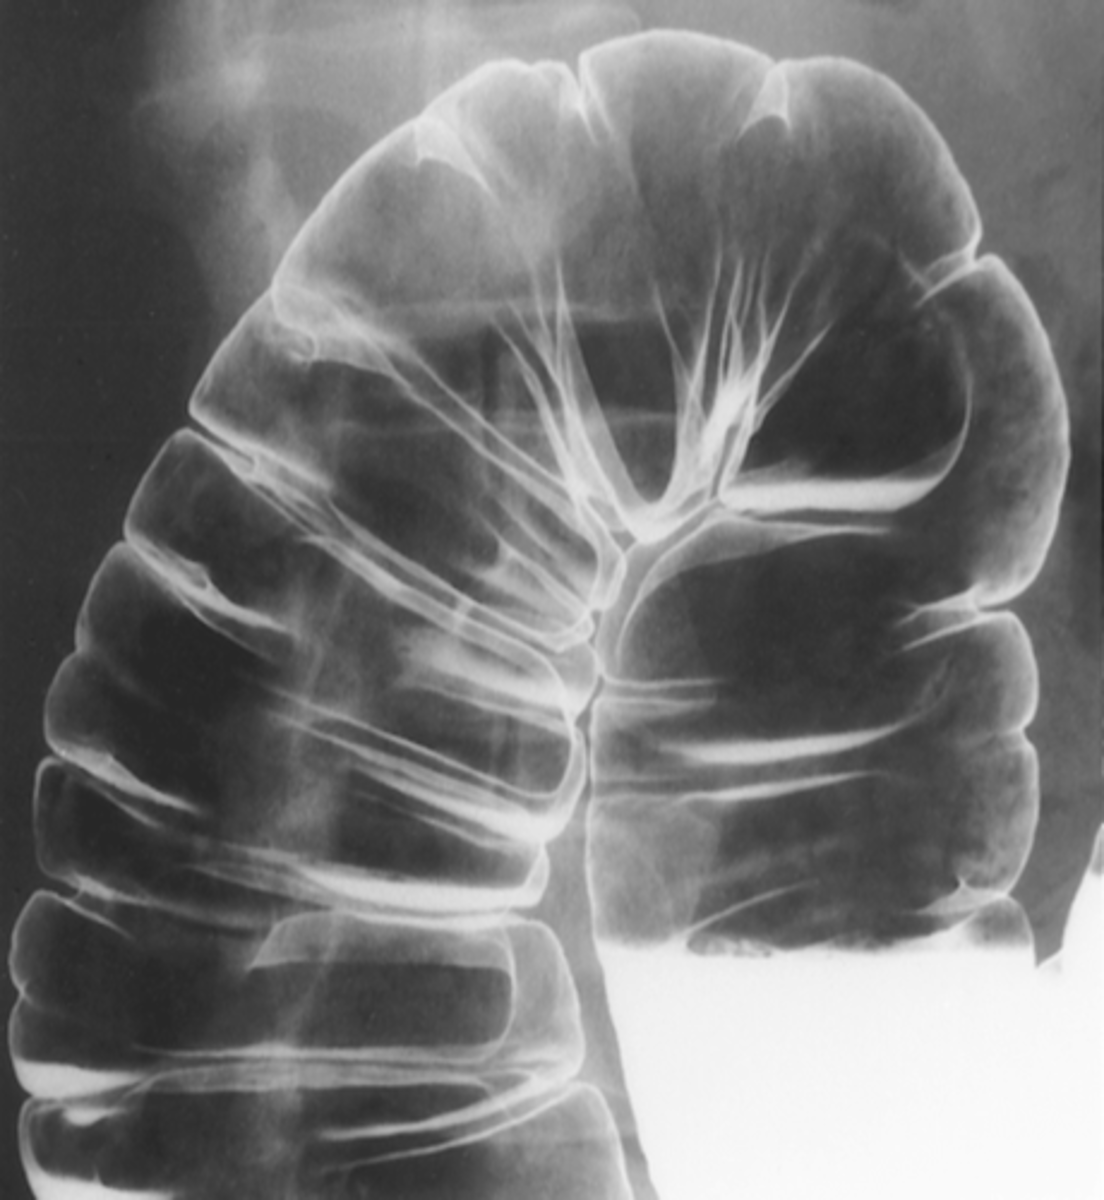

Valvulae connivente

Look like a stack of coins

What do we call the thin, circumferential (complete) folds that are found in the small bowel?

Haustra --> large bowel

What fold is this and where is it found?

Valvulae vonnivente --> small bowel